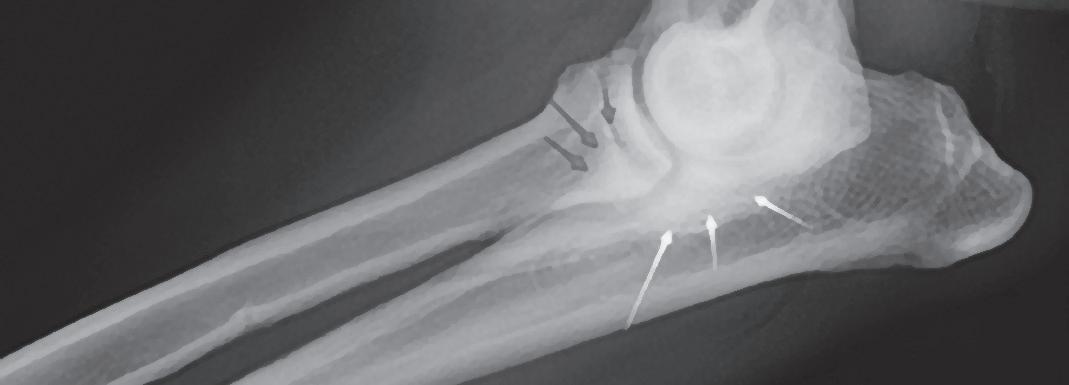

Se realiza la necropsia en la que se observa el corazón dentro del saco pericárdico con abundante líquido pericárdico. Se observa una gran masa redondeada de 7 x 5 x 3 cm en la base de la aorta, de consistencia firme, vascularizada, la cual al corte presenta vascularización y cavitaciones, áreas de hematoma y áreas de tejido graso y tejido fibroso. Se observa engrosamiento y degeneración de ambas válvulas atrioventriculares y, además, presencia de un nódulo en la válvula tricúspide de aspecto liso, color beige, no vascularizado de 1,5 cm. Se realizó en la toma y envío de muestras de las lesiones observadas en la base de corazón y tricúspide (Figs. 7, 8, 9 y 10). El análisis histopatológico de ambas lesiones confirma la sospecha diagnóstica de quemodectoma, siendo el nódulo tricúspide metástasis de la neoplasia principal en la base aórtica (Fig. 11), ya

Figura 7. Imagen de corazón evidenciando masa en base aórtica (flecha). Figura 8. Detalle de masa adherida a aorta. Masa esponjosa, cavitada, vascularizada, con áreas de necrosis y tejido adiposo. Figura 9. Detalle de masa tricúspide (flecha). Visión desde aurícula derecha. Figura 10. Detalle de masa tricúspide (flecha) adherida a las valvas. Vista gracias a la apertura completa del ventrículo derecho.

que al examen microscópico en ambas localizaciones se observaron células de bordes indefinidos, citoplasma escaso a moderado eosinófilo finamente granular, núcleo redondo, cromatina granular y nucléolo variablemente presente, pequeño, redondo y basófilo. También se observó anisocitosis y anisocariosis moderadas. Se reconocieron mitosis en 10 campos de 40X a través de la autólisis en la muestra. Se diagnosticó así en la muestra de aorta y tejido adiposo de la base cardíaca un carcinoma neuroendocrino, consistente con quemodectoma, con invasión intravascular. En la muestra de la válvula tricúspide y miocardio de la pared ventricular derecha se diagnosticó metástasis valvular miocárdica de carcinoma neuroendocrino y degeneración mixomatosa de la válvula tricúspide, marcada, crónica y difusa (endocardiosis). Además, la lesión neoplásica en tricúspide presentaba carácter infiltrativo hacia el tejido miocárdico de la pared ventricular derecha y epicardio (Fig. 12).